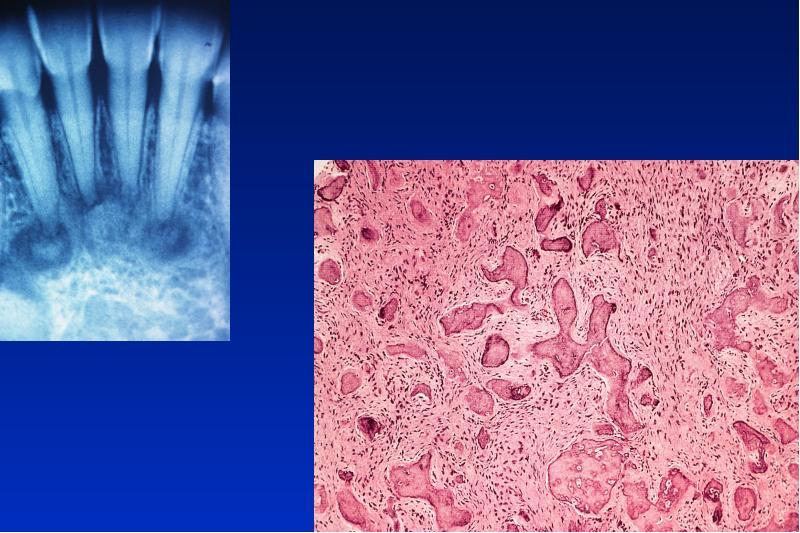

- 56. Odontom complex = gemischt compound